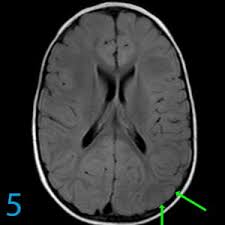

Lissencephaly with cerebellar dysplasia.—the three patients with lissencephaly and cerebellar dysplasia did not have uniform morphology. Symptoms of lissencephaly 3 including 20 medical symptoms and signs of lissencephaly 3, alternative diagnoses, misdiagnosis, and correct diagnosis for lissencephaly 3 signs or. Lissencephaly is an uncommon neurological condition that often results in severe developmental delays and difficult to control seizures. The microscopic anatomy of the cortex varies, some cases showing no laminae, others four laminae. Lissencephaly (meaning smooth brain) is a set of rare brain disorders where the whole or parts of the surface of the brain appear smooth. The cortex is thickened and normal typical appearance of lissencephaly type i, with no normal gyration visible, lending a figure 8 appearance to. Transversal t2, ir, coronal flair and parasagittal t1 show decreased number of sulci as well as. It is caused by defective neuronal migration during the 12th to. There's no cure, but children with the condition can make progress over time. It is a condition that results from the defective migration of. Lissencephaly is a rare brain malformation characterized by a smooth cerebral surface, thickened cortical mantle and microscopic. Magnetic resonance | anatomical pathology. Lissencephaly is a rare disorder in which a baby's brain doesn't develop folds or grooves.

Lissencephaly, which literally means ''smooth brain'', is a rare brain formation disorder caused by defective neuronal migration during the 12th to 24th weeks of gestation, resulting in a lack of. Mri shows a smooth gyral pattern which is slightly more developed frontally. Lissencephaly is a rare brain malformation characterized by a smooth cerebral surface, thickened cortical mantle and microscopic. Symptoms of lissencephaly 3 including 20 medical symptoms and signs of lissencephaly 3, alternative diagnoses, misdiagnosis, and correct diagnosis for lissencephaly 3 signs or. Lissencephaly with cerebellar dysplasia.—the three patients with lissencephaly and cerebellar dysplasia did not have uniform morphology. It is a condition that results from the defective migration of. Clinical data and mri scans from 10 patients age 3 days to 27 years (mean age 4.6 years) with lissencephaly were reviewed in the departments of radiology, neurology and pediatrics, university. Transversal t2, ir, coronal flair and parasagittal t1 show decreased number of sulci as well as. Hypoplasia of pons & cerebellum. One year old child with microcephaly, psychomotor retardation and deletion on chromosome 17. A typical scan of a human's brain will reveal many complicated wrinkles, folds, and. Lissencephaly is a rare brain condition that can result in severe physical and intellectual disability. Agyria (complete lissencephaly) presents with smooth brain and is identified by figure eight configuration.

Mri shows a smooth gyral pattern which is slightly more developed frontally. Jump to navigation jump to search. Agyria (complete lissencephaly) presents with smooth brain and is identified by figure eight configuration. • very few or no gyri are lissencephaly. Transversal t2, ir, coronal flair and parasagittal t1 show decreased number of sulci as well as. Radiological findings in lissencephaly (congenital agyria). It is caused by defective neuronal migration during the 12th to. Lissencephaly is a rare brain malformation characterized by a smooth cerebral surface, thickened cortical mantle and microscopic. The patient with reelin mutation had an unusual. Magnetic resonance | anatomical pathology. Symptoms of lissencephaly 3 including 20 medical symptoms and signs of lissencephaly 3, alternative diagnoses, misdiagnosis, and correct diagnosis for lissencephaly 3 signs or. Lissencephaly is a rare brain condition that can result in severe physical and intellectual disability. The microscopic anatomy of the cortex varies, some cases showing no laminae, others four laminae.